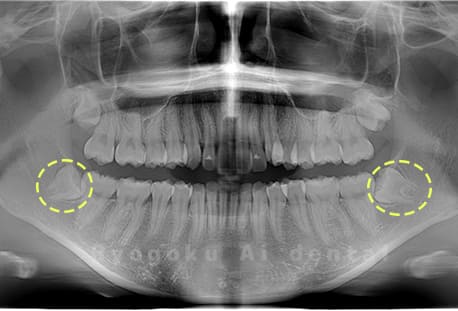

Case01

-

- 原因

- 水平埋伏智歯

- 治療内容

- 下顎の水平埋伏智歯を抜歯

<リスク・副作用>

手術後は痛み、腫れ、痺れなどの副作用が生じる場合があります。